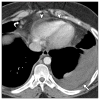

Results: The most common chest CT findings in this case series were pleural effusions and internal mammary and cardiophrenic lymphadenopathy. Pulmonary parenchymal findings included peripheral lung nodules of 1-3.5 cm in size with surrounding ground-glass opacity; many nodules had a linear track to the pleural surface that may correspond to the worm's burrow tunnel. Pericardial involvement (5/8 patients) and omental inflammation (5/7 patients), which are uncommon in Asian paragonimiasis, were common in this series.

Conclusion: Pleural and pulmonary features of North American paragonimiasis are generally similar to those reported from Asia. The presence of a track between a pulmonary nodule and the pleura may help distinguish paragonimiasis from mimickers, including chronic eosinophilic pneumonia, tuberculosis, fungal infection, or malignancy. Pericarditis, lymphadenopathy, and omental inflammation were more common in our series than in reports on paragonimiasis from other regions. These differences may be related to the infecting parasite species or to the fact that radiologic examinations in the present series were performed relatively early in the course of infection.